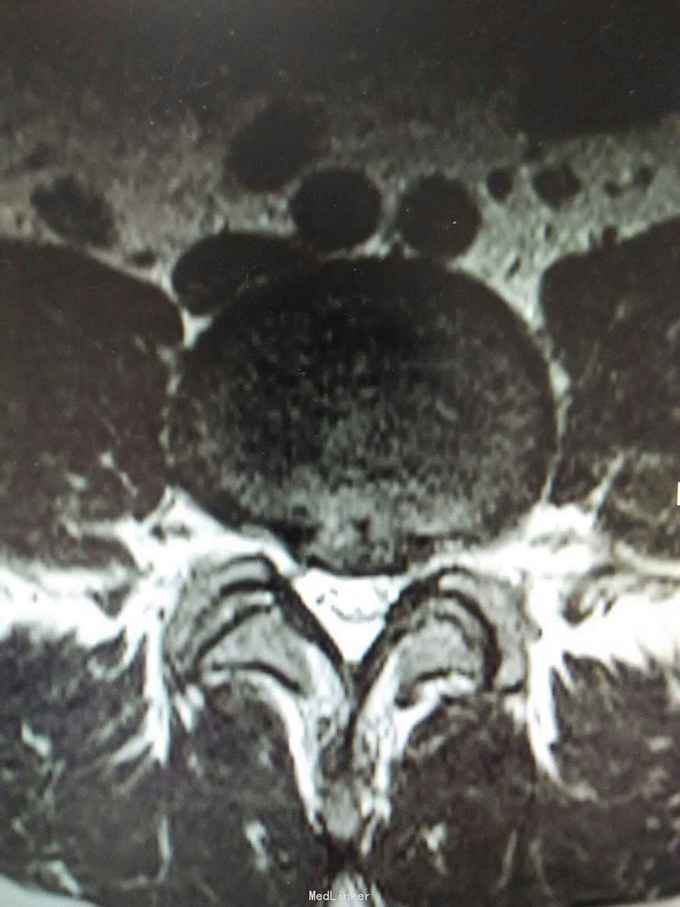

腰椎间盘突出 腰椎间盘突出症 骶管囊肿

1:腰椎间盘突出症2:骶管囊肿

该患者L4/5椎间盘中央突出,L5/S1椎间盘向左突出。手术右侧L4/5,L5/S1开窗,见骶1神经根与骶管囊肿粘连,压迫变性,水肿,变粗硬化。